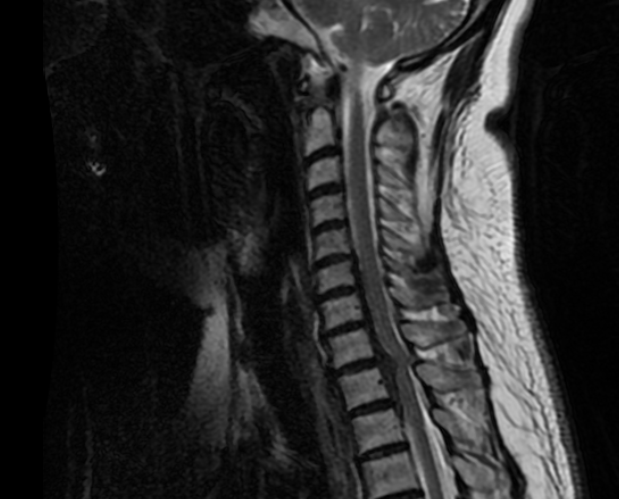

CASO CLÍNICO 1: HERNIA DISCAL TH1-TH2 MIGRADA CAUDALMENTE (con engrosamiento calcificado de LVCP hasta Th2-Th3).

Paciente de 58 años con dolor radicular refractario de >6 meses en MSD, acompañada de pérdida de fuerza en la musculatura intrínseca y atrofia muscular. EMG presenta afectación severa crónica en raíces C7-C8-Th1 derechas.

Obsérvese HDTh1-Th2 con migración caudal retrosomática (Th2)

Obsérvese el engrosamiento de LVCP de aspecto calcificado

El compromiso anterior del canal (a pesar de la radiculopatía severa en MSD) me obliga a plantearme un abordaje anterior con posibilidad de ampliar el campo a través de una esternotomía.